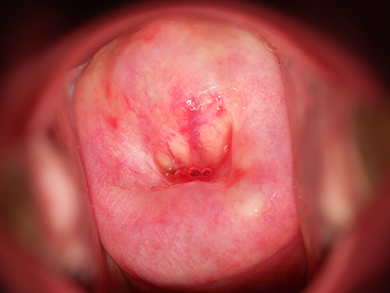

偏光

表面の反射を抑え、子宮頸部内面の状態を観察しやすくします。